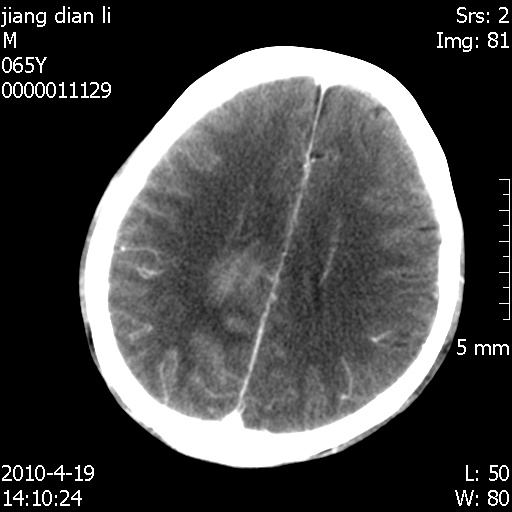

老年男性,突发左下肢无力1天,其余有价值的检查都没有。平扫ct值大约60hu,增强后ct值没什么改变,请大家讨论一下这个病例是什么?说明诊断理由。

左小脑、右大脑顶叶多发圆形高密度病灶,其周环状低密度影。考虑多发脑出血。隔期观察。

今天上班后发现病人前天复查(4月18日发病,19日初诊,22日复查),三个病灶均明显增大,边缘仍旧清楚,水肿加重,右侧脑室基本闭塞。

基于这样的表现,不知大家有什么看法?(临床其他检查我还没有追踪)

我想:如果是肿瘤出血的话,一般不会导致体积明显改变,水肿又进一步加重;如果是出血灶,那么现在应该正好是水肿加重的时候,还是比较符合,但是为什么边缘又是这样的特点?